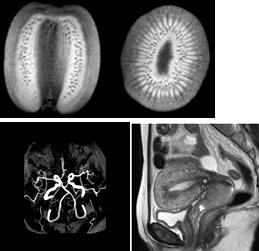

| 右の画像は、くだもののキウイをMR装置で撮像した縦割りと横割りの画像です。白黒の画像ですが、キウイを食べるときに包丁で切った場面を想像してください。実物に近い鮮明な画像が得られます。 同様に人体を検査した場合も分かりやすい画像が得られます。また、部位によって薬(造影剤)を使わないでも右に示すような血管のみの画像を得ることもできます。 一回の撮像時間は3分程度の検査ですが、多くの種類の画像を撮像しますので、全体では20分程度の時間がかかります。 |

![]() |

| 脳血管の画像 | 女性の子宮の画像 | |